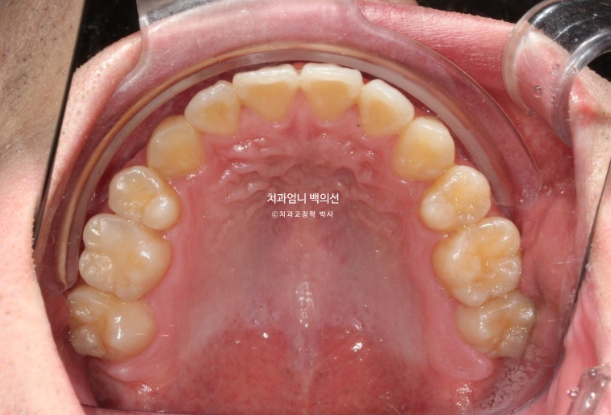

25.04

22.09~25.04

치근흡수는 없으며 치근평행도는 양호합니다